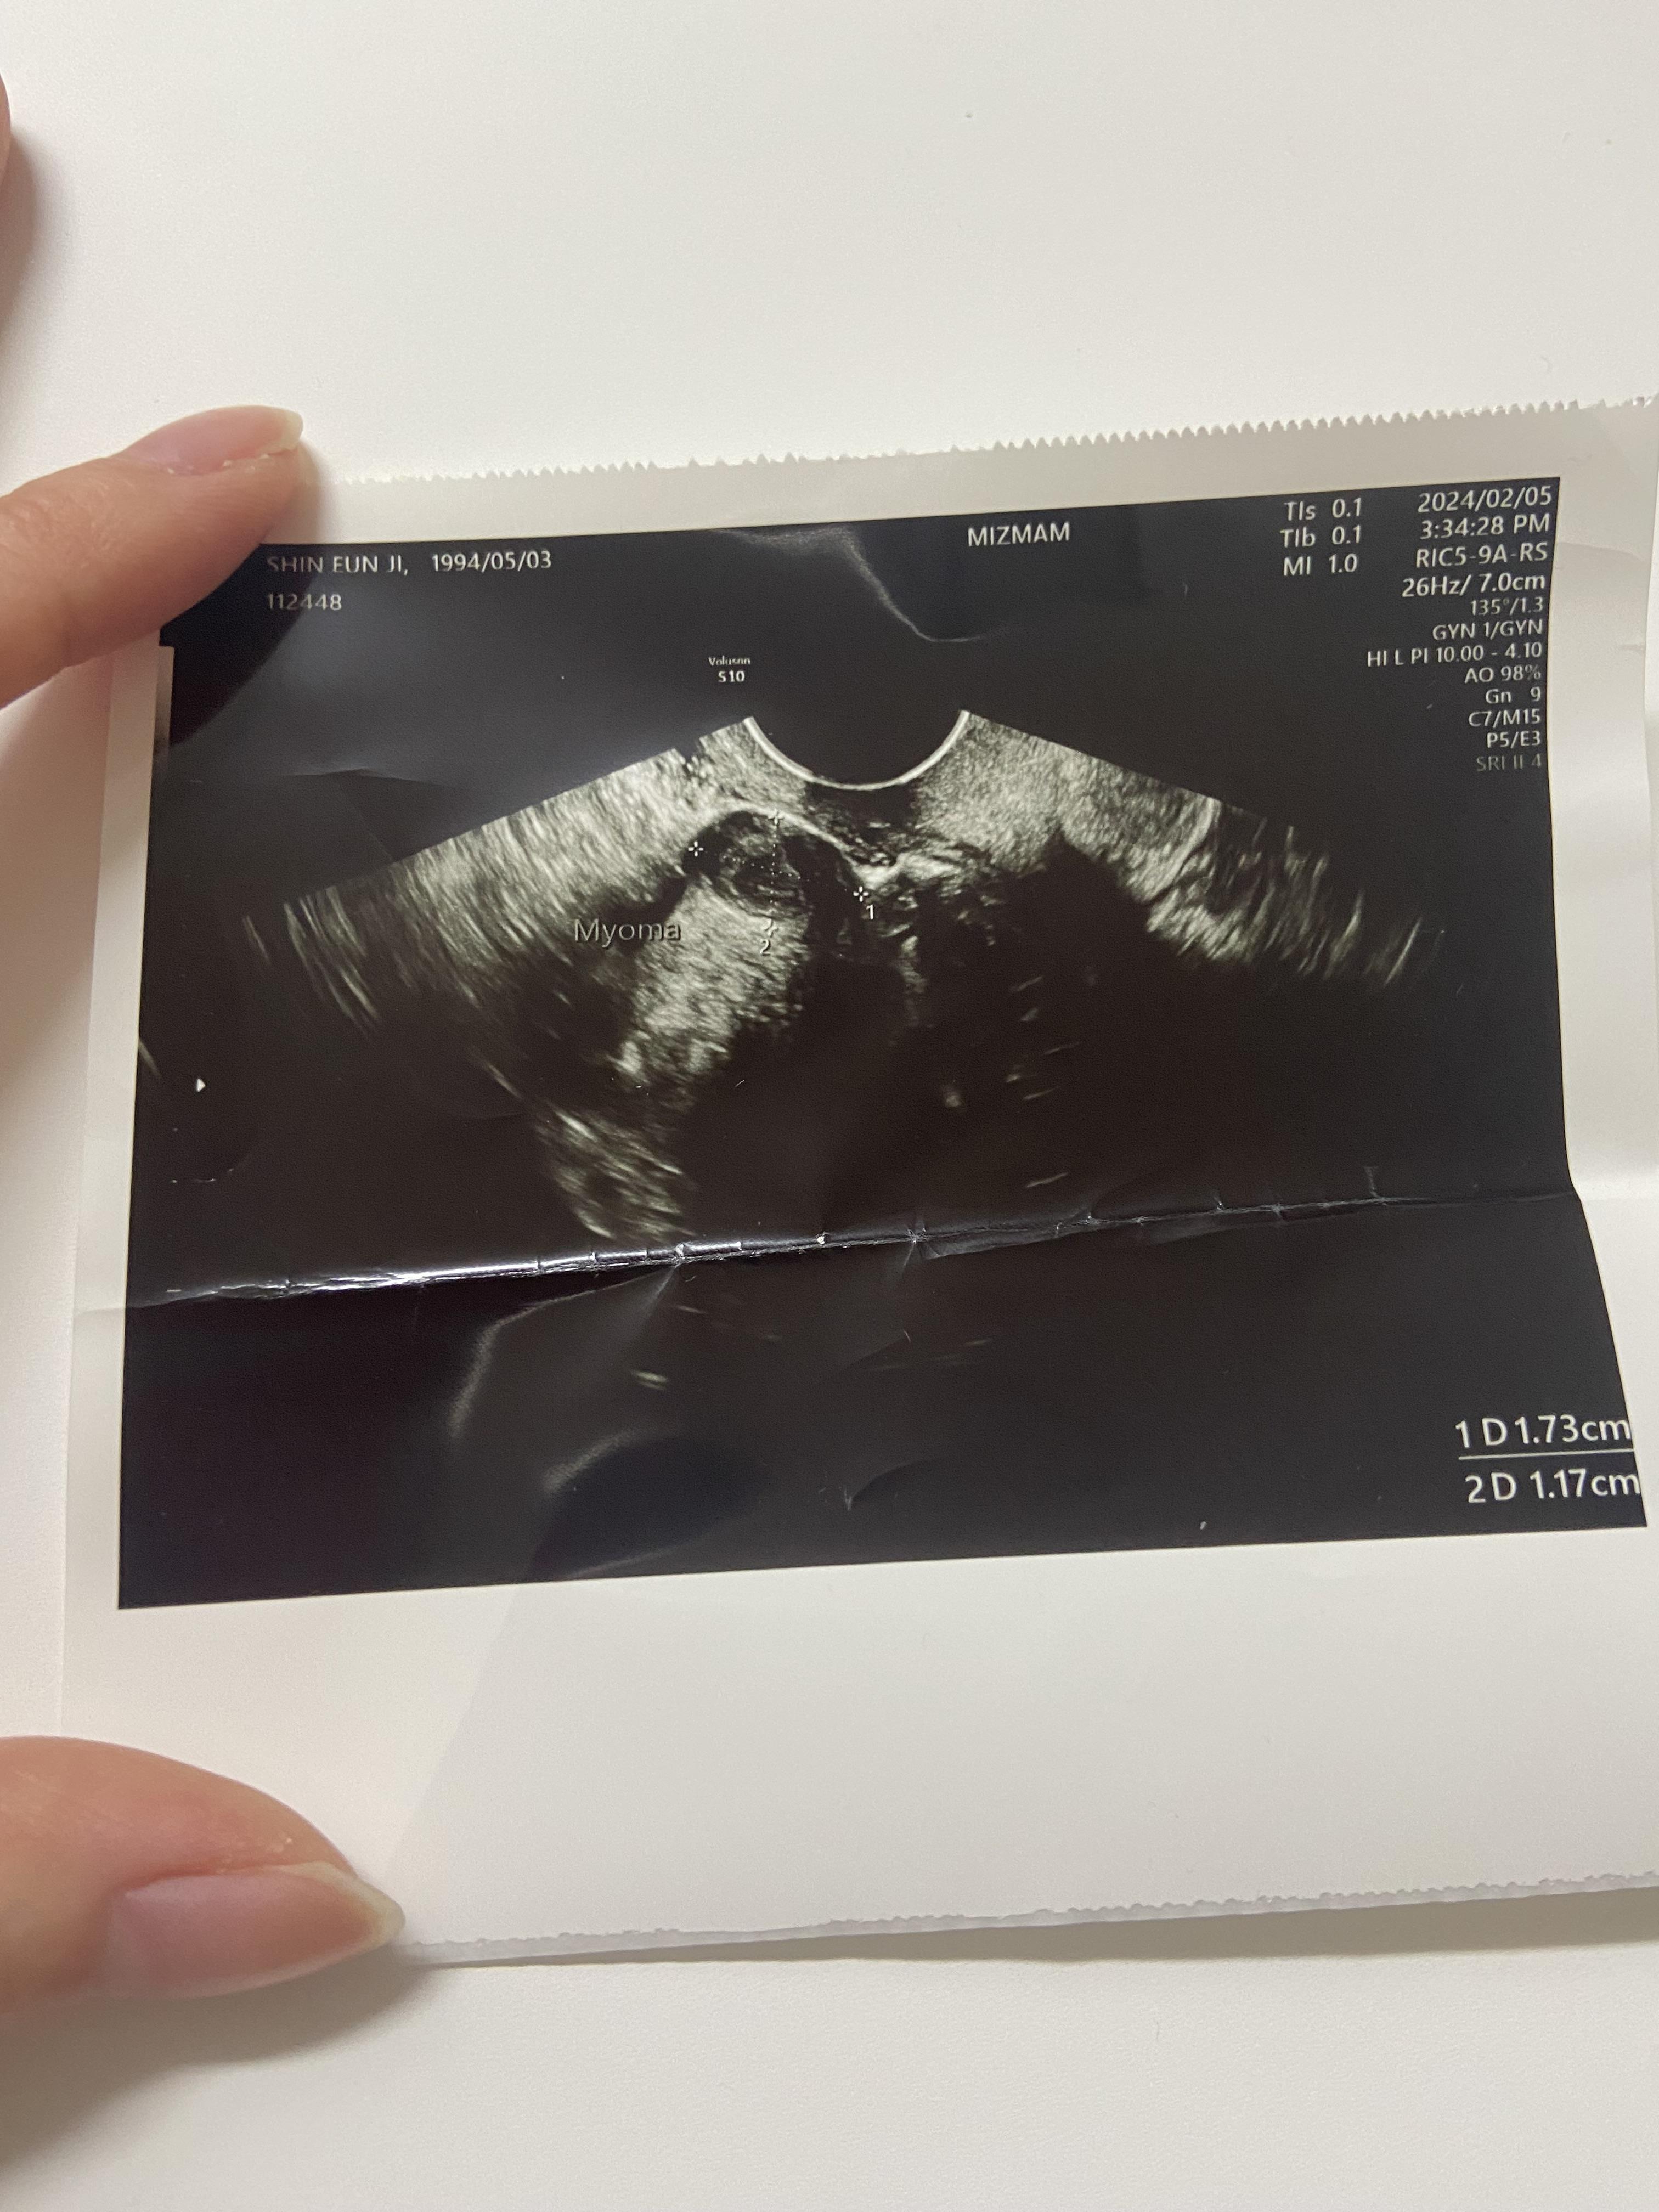

발견 된 것은 자궁 근종 뿐.... 뭔가 부끄러운 근종 사진ㅎㅎ

다행히 크기나 위치가 문제가 되지는 않는다고 하셨다. 그리고 의사쌤이 왜케 일찍 왔냐며... 한 소리 들었다. 아기집은 보이지 않았지만 자궁을 보시고는 임신일 것 같다고 흘려서 말씀하셨다. 그리고는 다음주에 오라고 하심.